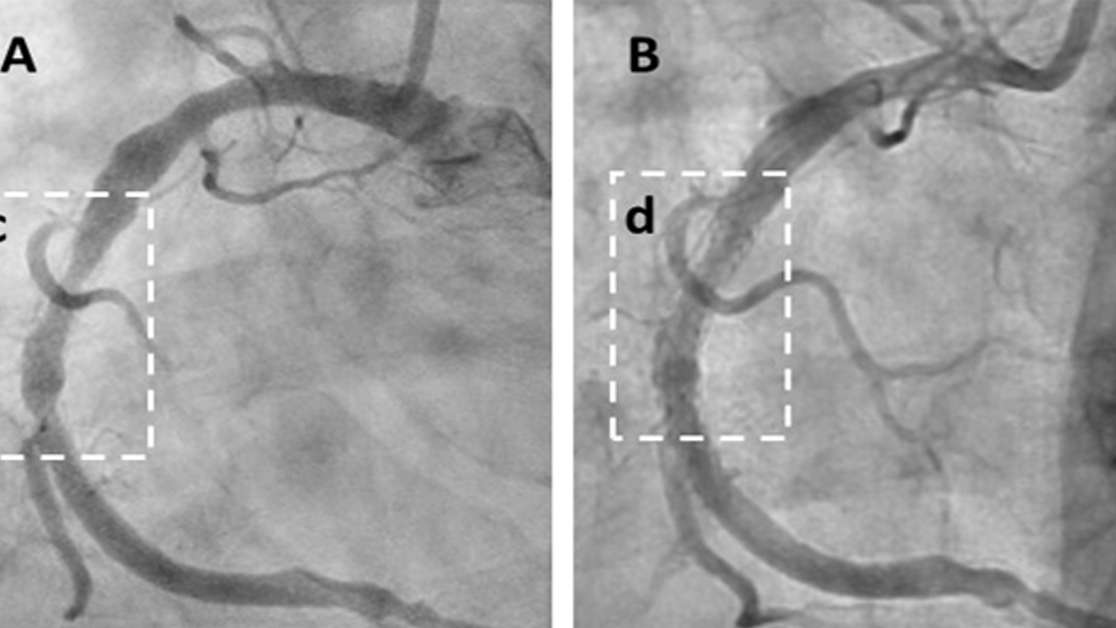

The clinical evidence presented is striking. In a documented subset of 20 patients with advanced, symptomatic angina, 18 (90%) reported significant clinical improvement—a rate that is highly statistically significant (P<0.0001) compared to expected spontaneous improvement. This subjective relief was corroborated by objective imaging data, including unprecedented reversals in Coronary Artery Calcium (CAC) scores (e.g., a reduction from 591 to 521) and angiographic evidence of reduced arterial narrowing, such as a 70% blockage in a critical coronary artery being reduced to just 27%. The late Professor Laurie G. Howes, a co-author of the paper and a pre-eminent Australian cardiologist with over 40 years of experience, concluded after reviewing the data that the therapy "may represent the greatest pharmacological development in cardiology since the introduction of statins." He noted that it "removes cholesterol from diseased arteries at a rate much faster than can be achieved by any other method currently available." The development of Cavadex has been championed by the Australian company Cholrem, founded by Kyle Hodgetts, a patient with recurrent heart disease who was failed by conventional treatments, discovered the preclinical research on cyclodextrin and became the first human to trial it for this purpose. Cholrem is pioneering this therapy in the face of a pharmaceutical industry that has largely overlooked the non-patentable molecule. Because HPβCD has been used safely for decades as a drug delivery vehicle and cannot be patented for a new use, it has failed to attract the large-scale investment typical for blockbuster drugs, despite its enormous therapeutic potential. Dr. James C. Roberts, a U.S. board-certified invasive cardiologist and co-author of the paper who has treated hundreds of patients with the therapy, described the benefits as "remarkable." He stated, "We are seeing rapid and profound symptomatic improvement in our highest-risk patients, corroborated by objective data showing plaque regression. The therapy is exceptionally well-tolerated, leveraging a molecule that has an established safety profile with both TGA and FDA approval for other uses. It works by stimulating the body's natural vascular repair program." The paper concludes that while the findings are preliminary, their consistency and magnitude provide a clear and urgent mandate for the initiation of large-scale, randomized controlled trials. Cholrem and its network of clinical collaborators are calling on the global medical community to validate these findings for the benefit of the millions of people suffering from heart disease worldwide. About Cholrem Pty Ltd: Cholrem Pty Ltd is an Australian pharmaceutical research company dedicated to advancing cyclodextrin-based therapies for the treatment of atherosclerotic cardiovascular disease. Founded by Kyle Hodgetts, the company is committed to developing and providing access to innovative treatments that have the potential to reverse the world's number one killer. Over the past four years, Cholrem has supplied over 20,000 units of its product to patients globally. Media Contact: Kyle Hodgetts, Founder & CEO Cholrem Pty Ltd [email protected]